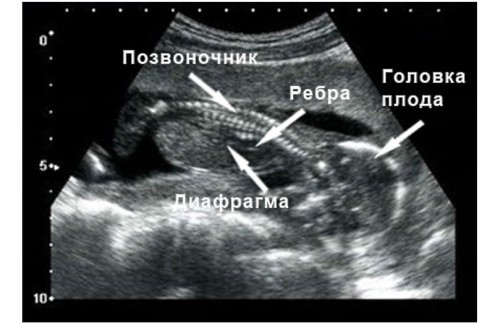

На 16 неделе малшыш весит приблизительно 80-100 г, а его рост колеблется в пределах 10-12 см. По размеру он похож на небольшое авокадо или средний помидорчик. Уже сформировалась система кроветворения и можно определить группу крови и резус. Малыш уже держит головку прямо и может вертеть ею из сторны в сторону. Начинают постепенно работать кишечник, желчный пузырь и печень. Также работают почки и мочевой пузырь, малыш начинает ходить "по-маленькому" и делает это довольно часто — примерно каждые 45 минут. Однако повода для беспокойства нет. Околоплодные воды меняются около 10 раз в сутки и абсолютно стерильны. Половые органы четко диференциированы и на узи будущим родителям уже уверенно скажут пол малыша.

На середине второго триместра- 16ой неделе плод развивается и становится более пропорциональным.

Его рост составляет 10-12 сантиметров

А вес 80-90 грамм.